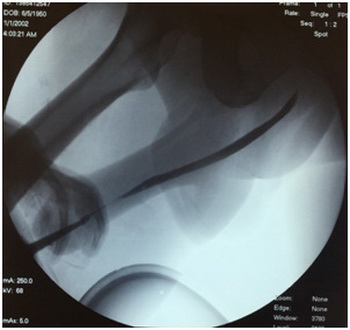

По данным ретроградной уретрографии определяется сужение в пенильном отделе уретры протяженностью до 3 см.

Пациенту выполнена операция по поводу рецидивирующей стриктуры уретры - буккальная пластика пенильного отдела уретры.